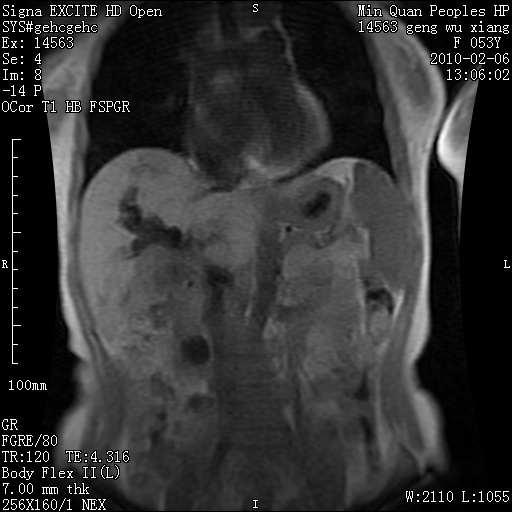

标题: MRI2762:胆道梗阻原因?

f,53y,全身黄染多日。

高位胆道梗阻 胆管癌可能性大

支持 高位胆道梗阻 胆管癌可能性大。